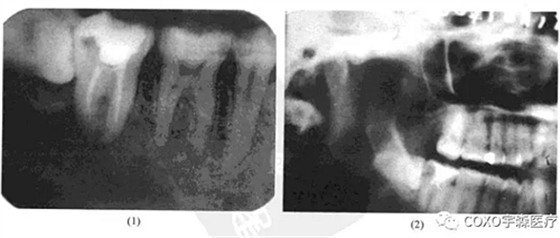

病例 女性,50歲,因[6區(qū)不適在某醫(yī)院攝片發(fā)現(xiàn)6根尖區(qū)有1.5cm×1.5cm陰影而來(lái)就診。檢查:[67已行單端固定橋修復(fù),無(wú)明顯叩痛與松動(dòng)。下頜全景片示:根尖陰影,周邊整齊,中央有一小游離骨塊狀物。牙片示陰影與[6根尖緊密接觸。疑為[6根尖周炎及局限性死骨形成(圖13-9),拆除[67單端固定橋,發(fā)現(xiàn)[6為活髓,行根管治療術(shù)后,手術(shù)探查,去除病變組織,病理最后診斷為牙骨質(zhì)骨化性纖維瘤。

牙骨質(zhì)骨化纖維瘤臨床上多發(fā)生在牙根部位,不僅有骨小梁形成,而且有牙骨質(zhì)形成,因而將其歸類(lèi)為牙源性腫瘤。在臨床上并不多見(jiàn),但其早期僅呈現(xiàn)根尖部頜骨內(nèi)病損時(shí),則易與根尖周病混淆。本病例病灶不大,位于根尖,牙片顯示陰影與[6關(guān)系十分密切,[6有冠修復(fù),但未見(jiàn)行根管治療術(shù),故疑為慢性根尖周炎;由于其中有一小團(tuán)密度與骨質(zhì)相似的鈣化影,故又疑是否為炎癥導(dǎo)致的死骨殘留。然而拆除[67單端固定橋后,發(fā)現(xiàn) 為活髓,就此否定了根尖周炎的診斷。最后經(jīng)手術(shù)證實(shí)為牙骨質(zhì)骨化性纖維瘤。本例的診治經(jīng)驗(yàn)提示:牙骨質(zhì)骨化性纖維瘤早期的 線片可呈不典型表現(xiàn)

(此患者的 線片表現(xiàn)與骨化性骨纖維瘤的多囊、骨質(zhì)鈣化、疏松不一等基本表現(xiàn)完全不一致);為排除根尖周病,牙髓是否有活力存在,也是關(guān)鍵的鑒別點(diǎn)